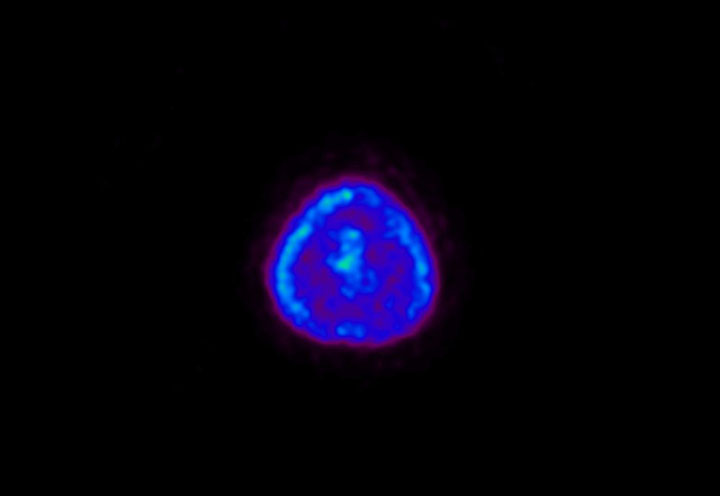

Head / Case5 : Amyloid

Coronal

Courtesy : Kindai University Hospital

- Imaging protocol

- Injected dose: 4.27 MBq/kg, 18F-Flutemetamol

- Uptake time: 99 minutes

- Scan time: 20 minutes